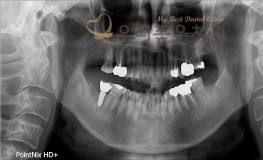

우리좋은치과 치아 상실 및 골소실 → 뼈이식 및 임플란트 보철 치료(임**2016...

No.296

임플란트

2019-05-31

1544